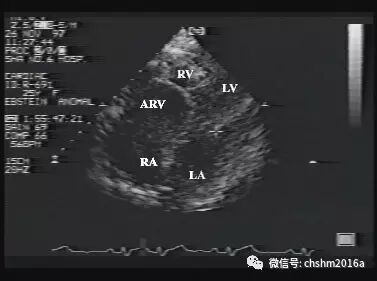

1.二维超声心动图

四腔心切面显示三尖瓣隔叶附着点向心尖方向下移,距二尖瓣前叶附着点大于15mm,二尖瓣前叶附着点仍位于瓣环部,瓣叶冗长,部分可粘附于右室心肌上,右室两腔心切面显示后叶下移。接近右室心尖小梁部。三尖瓣环径增大,功能右房明显增大。

彩超伪像是什么先天性心脏病超声诊断(超声梦影像医生集团 CCM)_https://www.jmylbn.com_新闻资讯_第17张

图2.3.15   心尖四腔观显示房化右室

ARV:房化右室  RA:右房   RV:右室  LA:左房  LV:左室